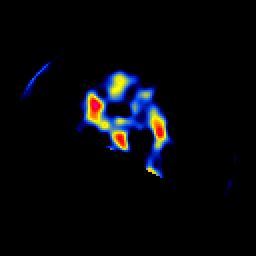

SPECT TL Study #5 -- Slice #51

[Home][Help][Clinical][Tour 1][Tour 2][Tour 3] Slice 51